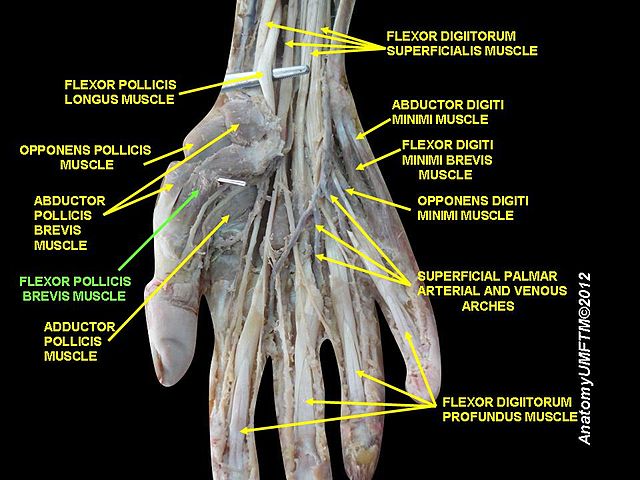

El músculo flexor corto del dedo pulgar forma parte de la eminencia tenar junto con otros tres músculos. Este grupo muscular se ubica en la base del dedo pulgar y se encargan de flexionar y mover el dedo pulgar hacia adentro, para realizar el movimiento de oposición del pulgar o pinza.

Se encuentra ubicado en posición medial e inferior al músculo abductor corto del pulgar y por encima del oponente del pulgar.

Consta de dos vientres musculares llamados superficial y profundo, que tienen orígenes diferentes en los huesos del carpo.

La porción superficial se origina en la saliente lateral del hueso trapecio. Algunas veces se encuentra un haz muscular que está anclado a la lámina fibrosa del retináculo de los flexores.

El origen de la porción profunda es en dos de los huesos del carpo. Alcanza la cara lateral del trapezoide y la cara medial del grande. Este vientre se encuentra íntimamente relacionado con el músculo flexor largo del pulgar.

Distalmente termina uniéndose con el fascículo superficial para formar un solo músculo que termina en el dedo pulgar.

Tanto la porción superficial como la profunda se convierten en una estructura tendinosa. Después de recorrer una parte del camino junto al flexor largo del pulgar, el fascículo profundo termina uniéndose al superficial.

Formando un tendón único, el flexor corto del pulgar se inserta en la base de la falange proximal del pulgar y en el hueso sesamoideo que se encuentra inmerso en los ligamentos que forman parte de esa articulación.

En cuanto a la inervación, esta es diferente para el vientre superficial y el profundo, por lo que ha sido motivo de estudio, investigación y controversia.

Estudios científicos realizados midiendo los impulsos nerviosos del músculo, evidencian que el haz superficial recibe inervación motora a través del nervio mediano.

Por su parte, el vientre profundo está inervado por la rama profunda del nervio ulnar o cubital.